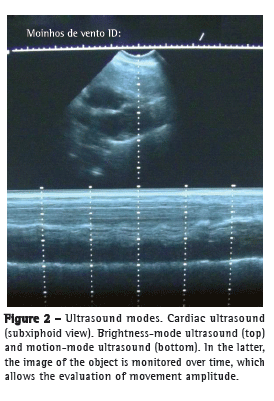

The way in which the reflected signals are processed determines image formation. When brightness-mode (B-mode) ultrasound is used, the amplitude of energy is shown as dots of varying intensity, which allows conventional two-dimensional image formation; when motion-mode (M-mode) ultrasound is used, the image of a given object is monitored over time (Figure 2).(5)

Initially, for B-mode ultrasound, the transducer is positioned with its marker directed to the head of the patient and perpendicular to the ribs, the typical lung ultrasound image being therefore obtained.(4,6) The adjacent intercostal spaces are examined by sliding the transducer vertically (Figure 3).(10)